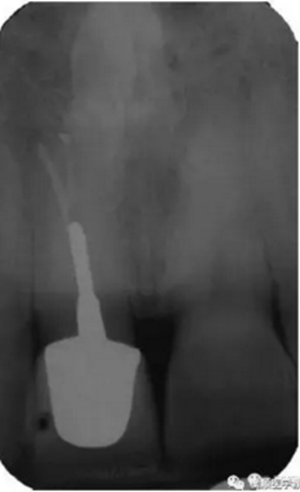

基于臨床檢查和X線片顯示,診斷為右上頜中切牙根尖周炎伴額外牙。治療計(jì)劃是先行患牙的根管治療,制作臨時(shí)義齒,最后制作樁核冠。應(yīng)用橡皮樟和顯微根管技術(shù),利用ProTaper旋轉(zhuǎn)銼配合使用 Hedstrom 銼和桉葉油,將根管內(nèi)充填物取出,觀察X線片可見(jiàn)根尖三分之一處主根管一分為二,確定另一根管的工作長(zhǎng)度,兩根管同行常規(guī)根管治療,充填后X線片顯示根管充填良好。樁核冠修復(fù)1年后,患牙無(wú)疼痛,影像檢查發(fā)現(xiàn)根尖顯影正常,根尖疾病治愈。

圖3. 樁核冠修復(fù)1年后患牙根尖周顯影